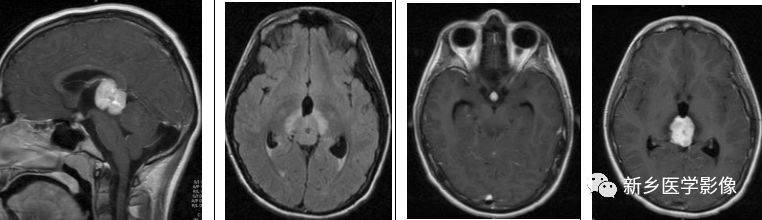

生殖细胞瘤是松果体区最常见的肿瘤。其好发于年轻男性,男女比约9:1.有时候,松果体区肿物可伴随鞍上肿物。肿瘤内无钙化,但可包绕松果体内钙化。有时,在T2WI上其可表现为稍高信号,小的囊变区可见。

矢状位及横断位T1WI+C示松果体区明显强化肿块,鞍上也可见小的强化肿块;横断位T2WI+FLAIR示松果体区高信号肿块伴周围水肿。